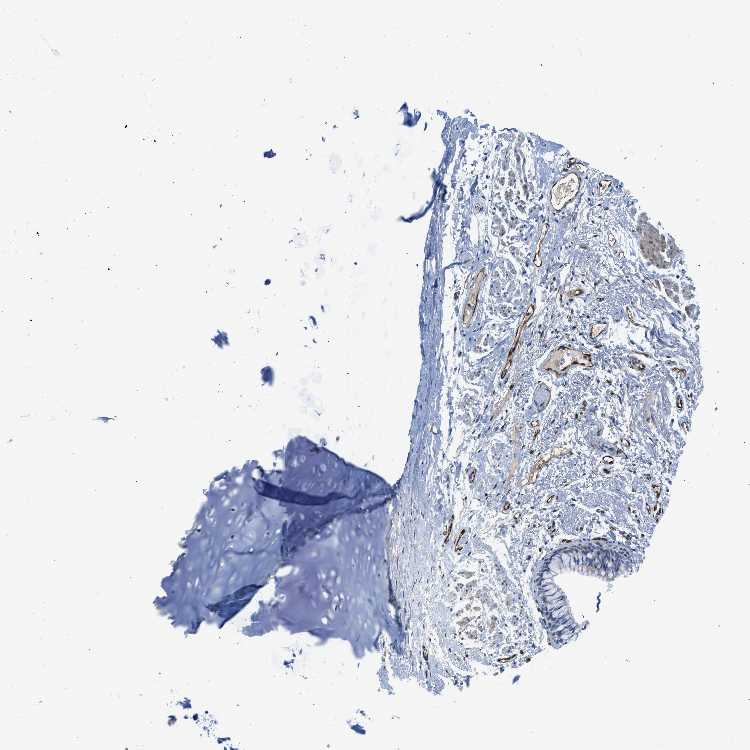

SOFT TISSUE 1 - Antibody stainingi

Antibody staining in the annotated cell types in the current human tissue is reported as not detected, low, medium, or high, based on conventional immunohistochemistry profiling in selected tissues. This score is based on the combination of the staining intensity and fraction of stained cells.

Each image is clickable and will lead to virtual microscopy that enables deeper exploration of all samples and also displays staining intensity scores, fraction scores and subcellular localization as well as patient and tissue information for each sample.

Antibody HPA013169

Chondrocytes Not detected

Fibroblasts Not detected

Peripheral nerve Low

SOFT TISSUE 2 - Antibody stainingi